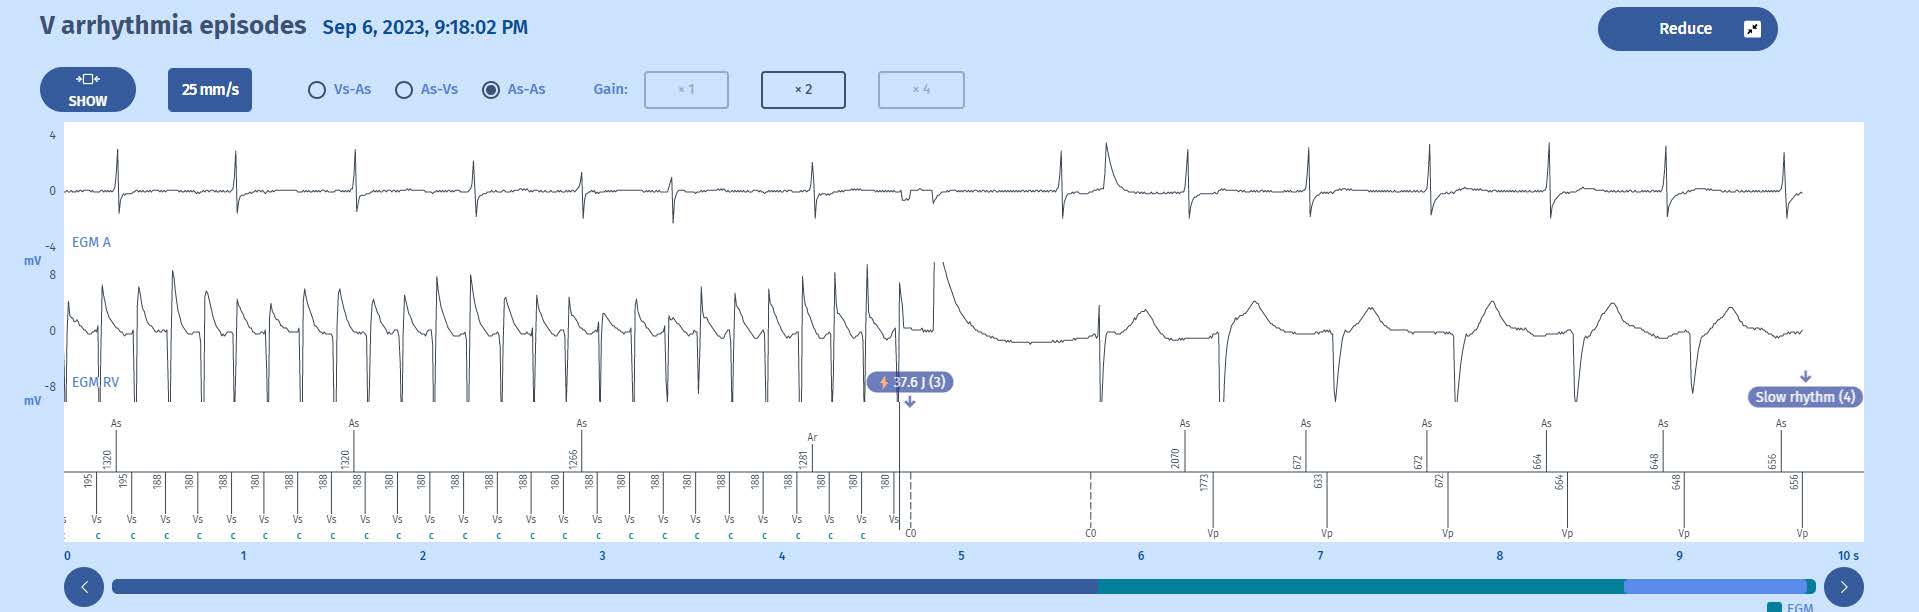

Electrogram: end

1 Once charged, the defibrillator sends a shock on the next cycle which is in the VF zone; shown by the marker: 37.6J (3).

2 After the shock, there is a 1-second blanking period (between C0 markers). After six cycles out of tachycardia zones the Slow rhythm majority is met (6/8) and the episode is terminated.